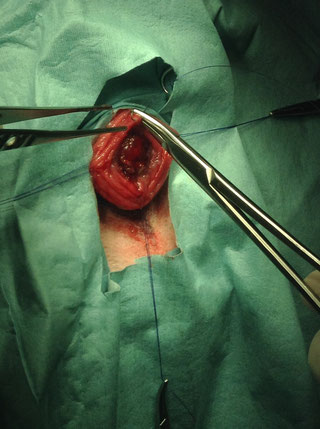

腫瘍化した右心耳にサチンスキーで腫瘍基部と右心房の間隙をクランプする。牽引後、TA30Vを挿入しステープリングを行う。

※腫瘍化した右心耳にアプローチしている所。術後には抗癌剤治療が行われます。